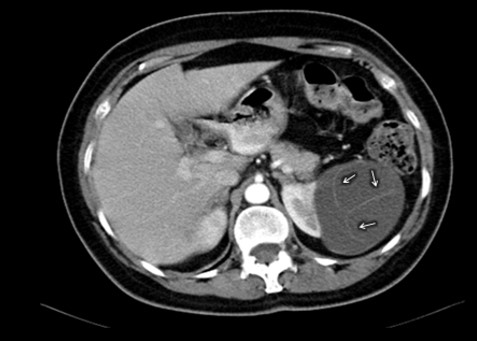

La Categoría IV presenta captación de un componente sólido intra quístico, muestra realces nodulares fuera de la pared y de los septos interpuestos en el área quística compleja, calcificaciones gruesas, vascularizadas con un importante realce con contraste yodado IV. En realidad, son lesiones malignas con componente quístico. Se trata de neoplasias quísticas, y precisan cirugía y estadificación.(19, 21) (Anexos 11 y 12).